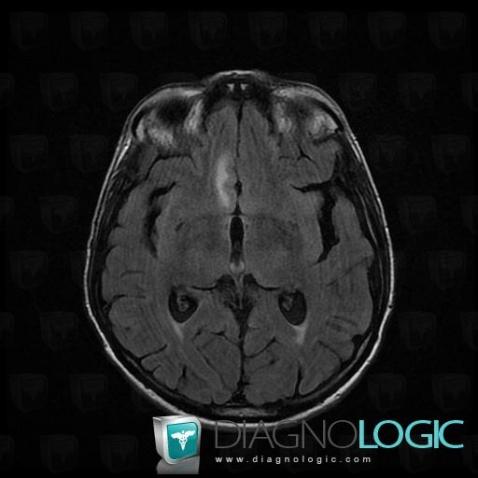

Les images ci-dessous illustrent ce dossier pour les diagnostics Carcinose méningée, Méningite carcinomateuse, pour les modalités (IRM)

Voici les informations spécifiques à l'image clé ci dessus:

- Diagnostic Méningite carcinomateuse, Localisation(s) Région cortico sous corticale, comportant les gammes Lésion corticale